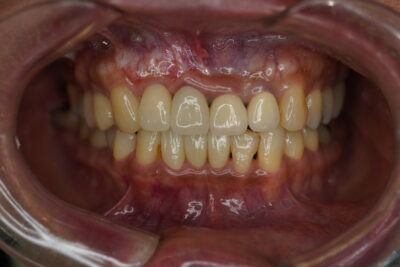

処置後Photoになります👀✨

今後はメンテナンスで定期的に通っていただく予定です🪥

🦷担当医:Dr.小林

🦷治療内容:根管治療・ファイバーコア・ジルコニアセラミック

🦷技工所:プロミネント